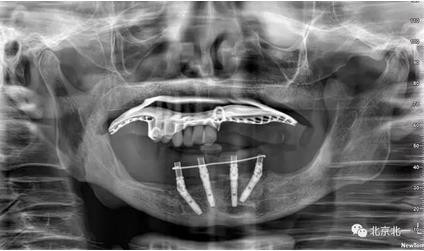

圖七:采用A04技術(shù),拔除下頜余留牙,修整骨平面。在頦孔前方傾斜植入兩枚植體,避開(kāi)頦孔。減少懸臂。前牙區(qū)植入兩枚直的植體。完成即刻修復(fù)。一日得牙,缺牙后多少年來(lái)都沒(méi)有吃過(guò)蘋果的滋味,到種植牙時(shí)代,想吃什么就吃什么, 我的健康我做主。